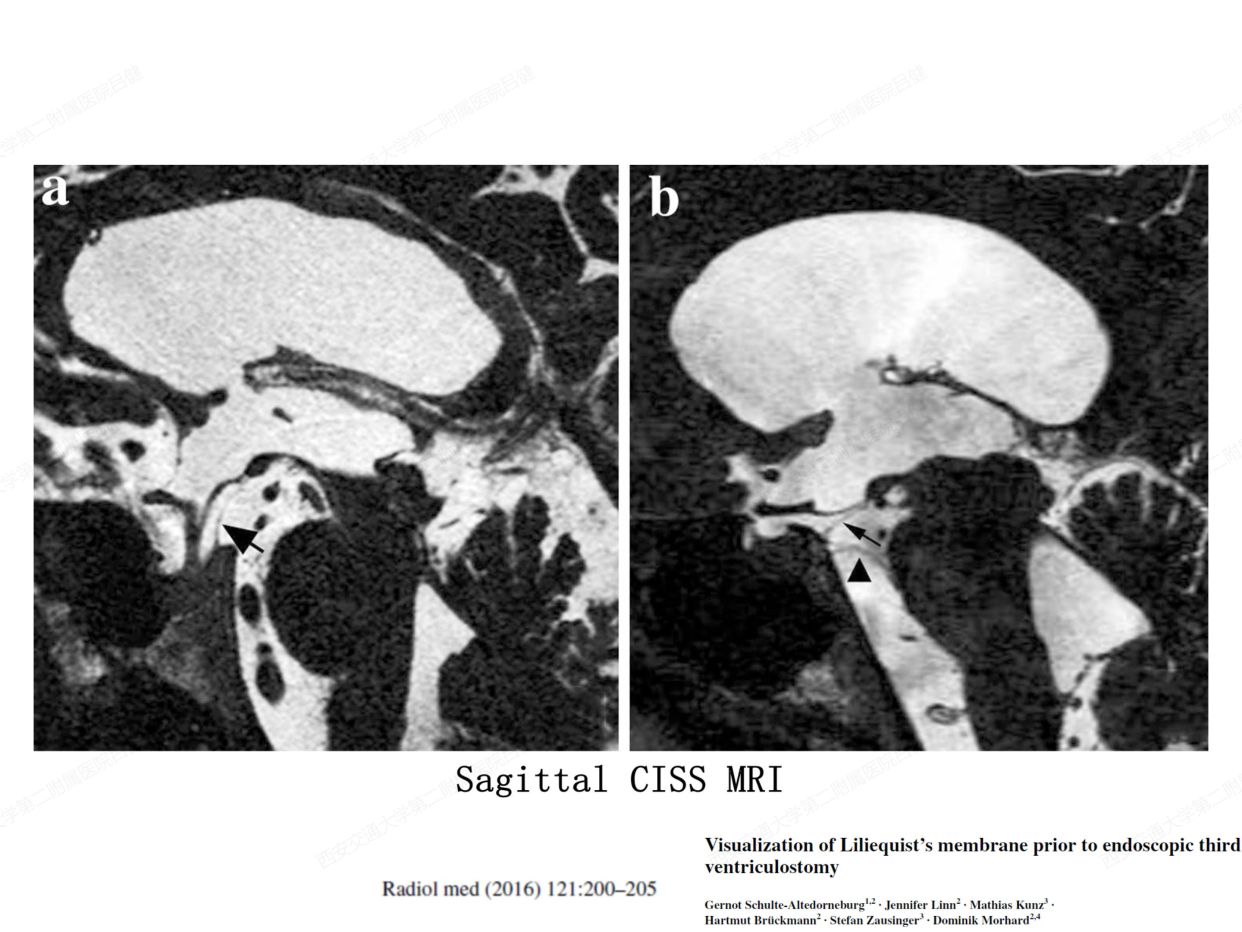

颅内蛛网膜和蛛网膜下池的解剖学研究意义

转自 神外前沿2020-6-22 解剖课件| 颅内蛛网膜和脑池的解剖研究-西交二院吕健